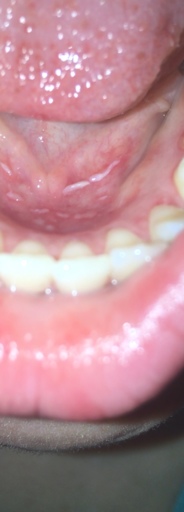

White stuff appearing in mouth?

Recently brushing my teeth, eating and drinking water has been leaving a stinging sensation in my mouth. Particularly around my gums sometimes but mostly on the floor of my mouth. I had a look and found these white stuff on the floor of my mouth. What is it?

From the picture, it appears you may be having an allergic reaction to whatever you are eating or possibly your toothpaste or mouthwash. Try to eliminate citrus and spicy food from your diet temporarily. If you recently switched your mouthwash or toothpaste, try and revert to your previous brand. Personally, I cannot use Crest Prohealth products, it causes my tissue to become white and slough off. Highly acidic foods such as citrus and spicy foods can irritate the tissues as well. The more bland your diet the better, temporarily while the areas heal.